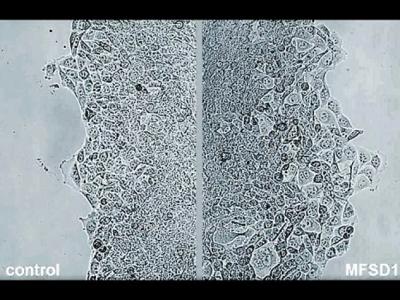

新研究发现蛋白质MFSD1可以通过将癌细胞

新研究发现蛋白质MFSD1可以通过将癌细胞粘在周围的组织上而阻止它们迁移(神秘的地...